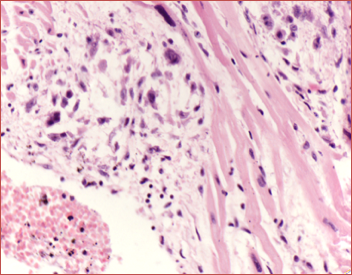

此种小体对诊断风湿病有意义。风湿小体的形成是在纤维素样坏死物质周边围绕数量不等的风湿细胞,它们是由增生的巨噬细胞吞噬纤维素样坏死物质转变而来,风湿细胞也称阿少夫细胞(Aschoff cell),有的文献称其为Anitschkow细胞。

风湿细胞体积较大,圆形、卵圆形,胞浆丰富,略嗜碱性,核大圆形或卵圆形,核膜清晰,核染色质集中于中央,横切面呈枭眼状,纵切面呈毛虫状。也可见多个核的Aschoff巨细胞。纤维素样坏死、成团的风湿细胞及伴有的淋巴细胞、浆细胞等共同组成的具有特征性的病变为风湿小体或阿少夫小体(Aschoff baody)。

(图3-2)